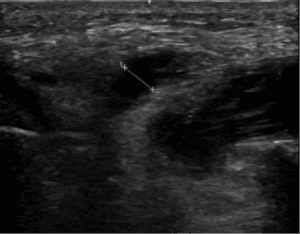

Point of care ultrasound (POCUS) was performed, with targeted views of the kidneys and bladder given the patient’s history of nephrolithiasis, as well as complete visualization of the aorta to the iliac bifurcation given the patient’s presentation with undifferentiated flank pain in accordance with emergency medicine POCUS recommendations [1-3]. The ultrasound revealing a large left renal stone with associated hydronephrosis (Figure 1A), a non-aneurysmal aorta, and an enlarged left iliac artery (Figure 1B, Video S1). The presence of the dilated left iliac artery prompted immediate consultative imaging rather than the common diagnostic pathway of next day outpatient consultative imaging. A CT scan confirmed the presence of multiple left-sided renal stones with hydronephrosis including a 2cm cluster in the renal pelvis (Figure 1C) and a 6.7cm ruptured left isolated iliac artery aneurysm (IAA; Figure 1D).

Figure 1. A) POCUS image of left kidney with large stone in the renal pelvis (blue arrow) and hydronephrosis. B) left iliac artery (blue chevrons). C) CT image of left kidney the renal pelvis stone (blue arrow) and lower pole non-obstructing stones (orange arrow) and D) left iliac artery with aneurysm (blue chevrons).

Video S1. First clip: left kidney with large stone in the renal pelvis and hydronephrosis. Second clip: left iliac artery.